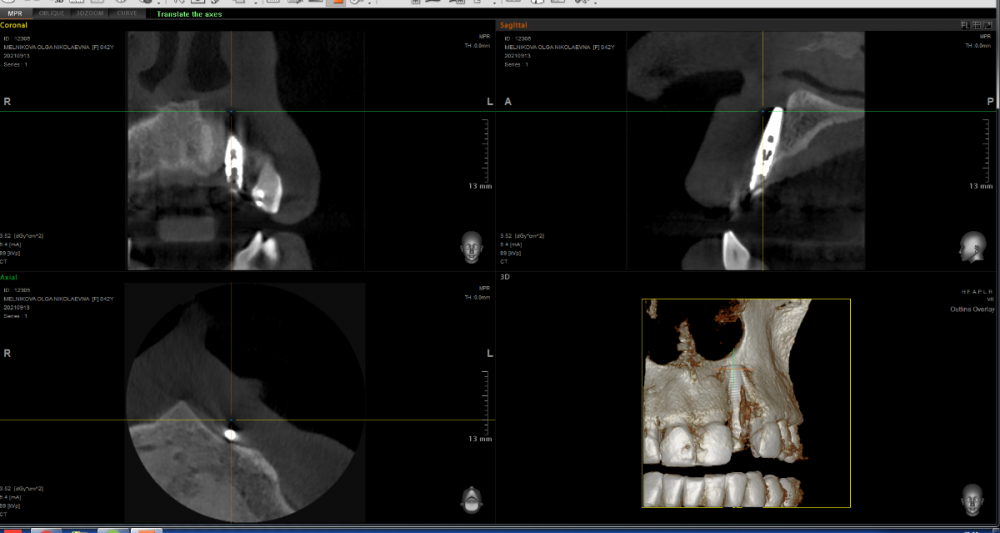

МОН Опубликовано 14 сентября, 2021 Автор Поделиться Опубликовано 14 сентября, 2021 Добрый вечер. Сделала вчера КТ зубов 21, 22, 23. Прилагаю часть срезов. Ссылка на комментарий

red_butler Опубликовано 15 сентября, 2021 Поделиться Опубликовано 15 сентября, 2021 2 минуты назад, МОН сказал: Интересно к чему я должна быть готова? к удалению импланта 1 2 Ссылка на комментарий

It'sGeorgy Опубликовано 15 сентября, 2021 Поделиться Опубликовано 15 сентября, 2021 Тему надо переименовать на «для чего делать КТ после имплантации и почему оптг в хирургии - бесполезная трата времени и денег» и показывать в ВУЗах. 1 Ссылка на комментарий

МОН Опубликовано 21 октября, 2021 Автор Поделиться Опубликовано 21 октября, 2021 Добрый день. Была недавно в клинике. Меня осматривал имплантолог и ортопед. Они посмотрели КТ, сказали, что по нему видно, как будто-то спереди импланта нет костной ткани. Проведя пальпацию пришли к выводу, что костная ткань прощупывается и имплан хорошо держится. Имплантолог сказал, что надо понаблюдать пол года. Подскажите, пожалуйста, что мне может грозить если имплант не будет удалён? Ссылка на комментарий